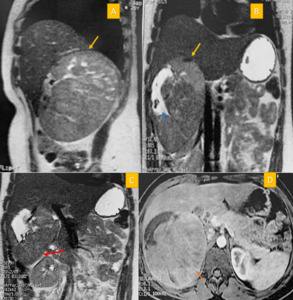

Abdominopelvic computed tomography (CT) shows an inter-hepatorenal tumor measuring 18 cm in its longest axis. Further characterization with abdominal magnetic resonance imaging (MRI) revealed a well-defined, solid, oval adrenal mass measuring 17cm in height,13.5 cm transversely, and 13cm anteroposteriorly. The tumor appeared hypointense on T1-weighted images and iso to hyperintense on T2-weighted images, with intense progressive contrast enhancement without washout. Despite its large size, the mass remained well-demarcated from adjacent structures, though it was in broad contact with the posterolateral segment of the right liver and caused compression of the retrohepatic vena cava (Figure 1).

__coronal_(b_c)_t2-weighted_sequence__an.png)